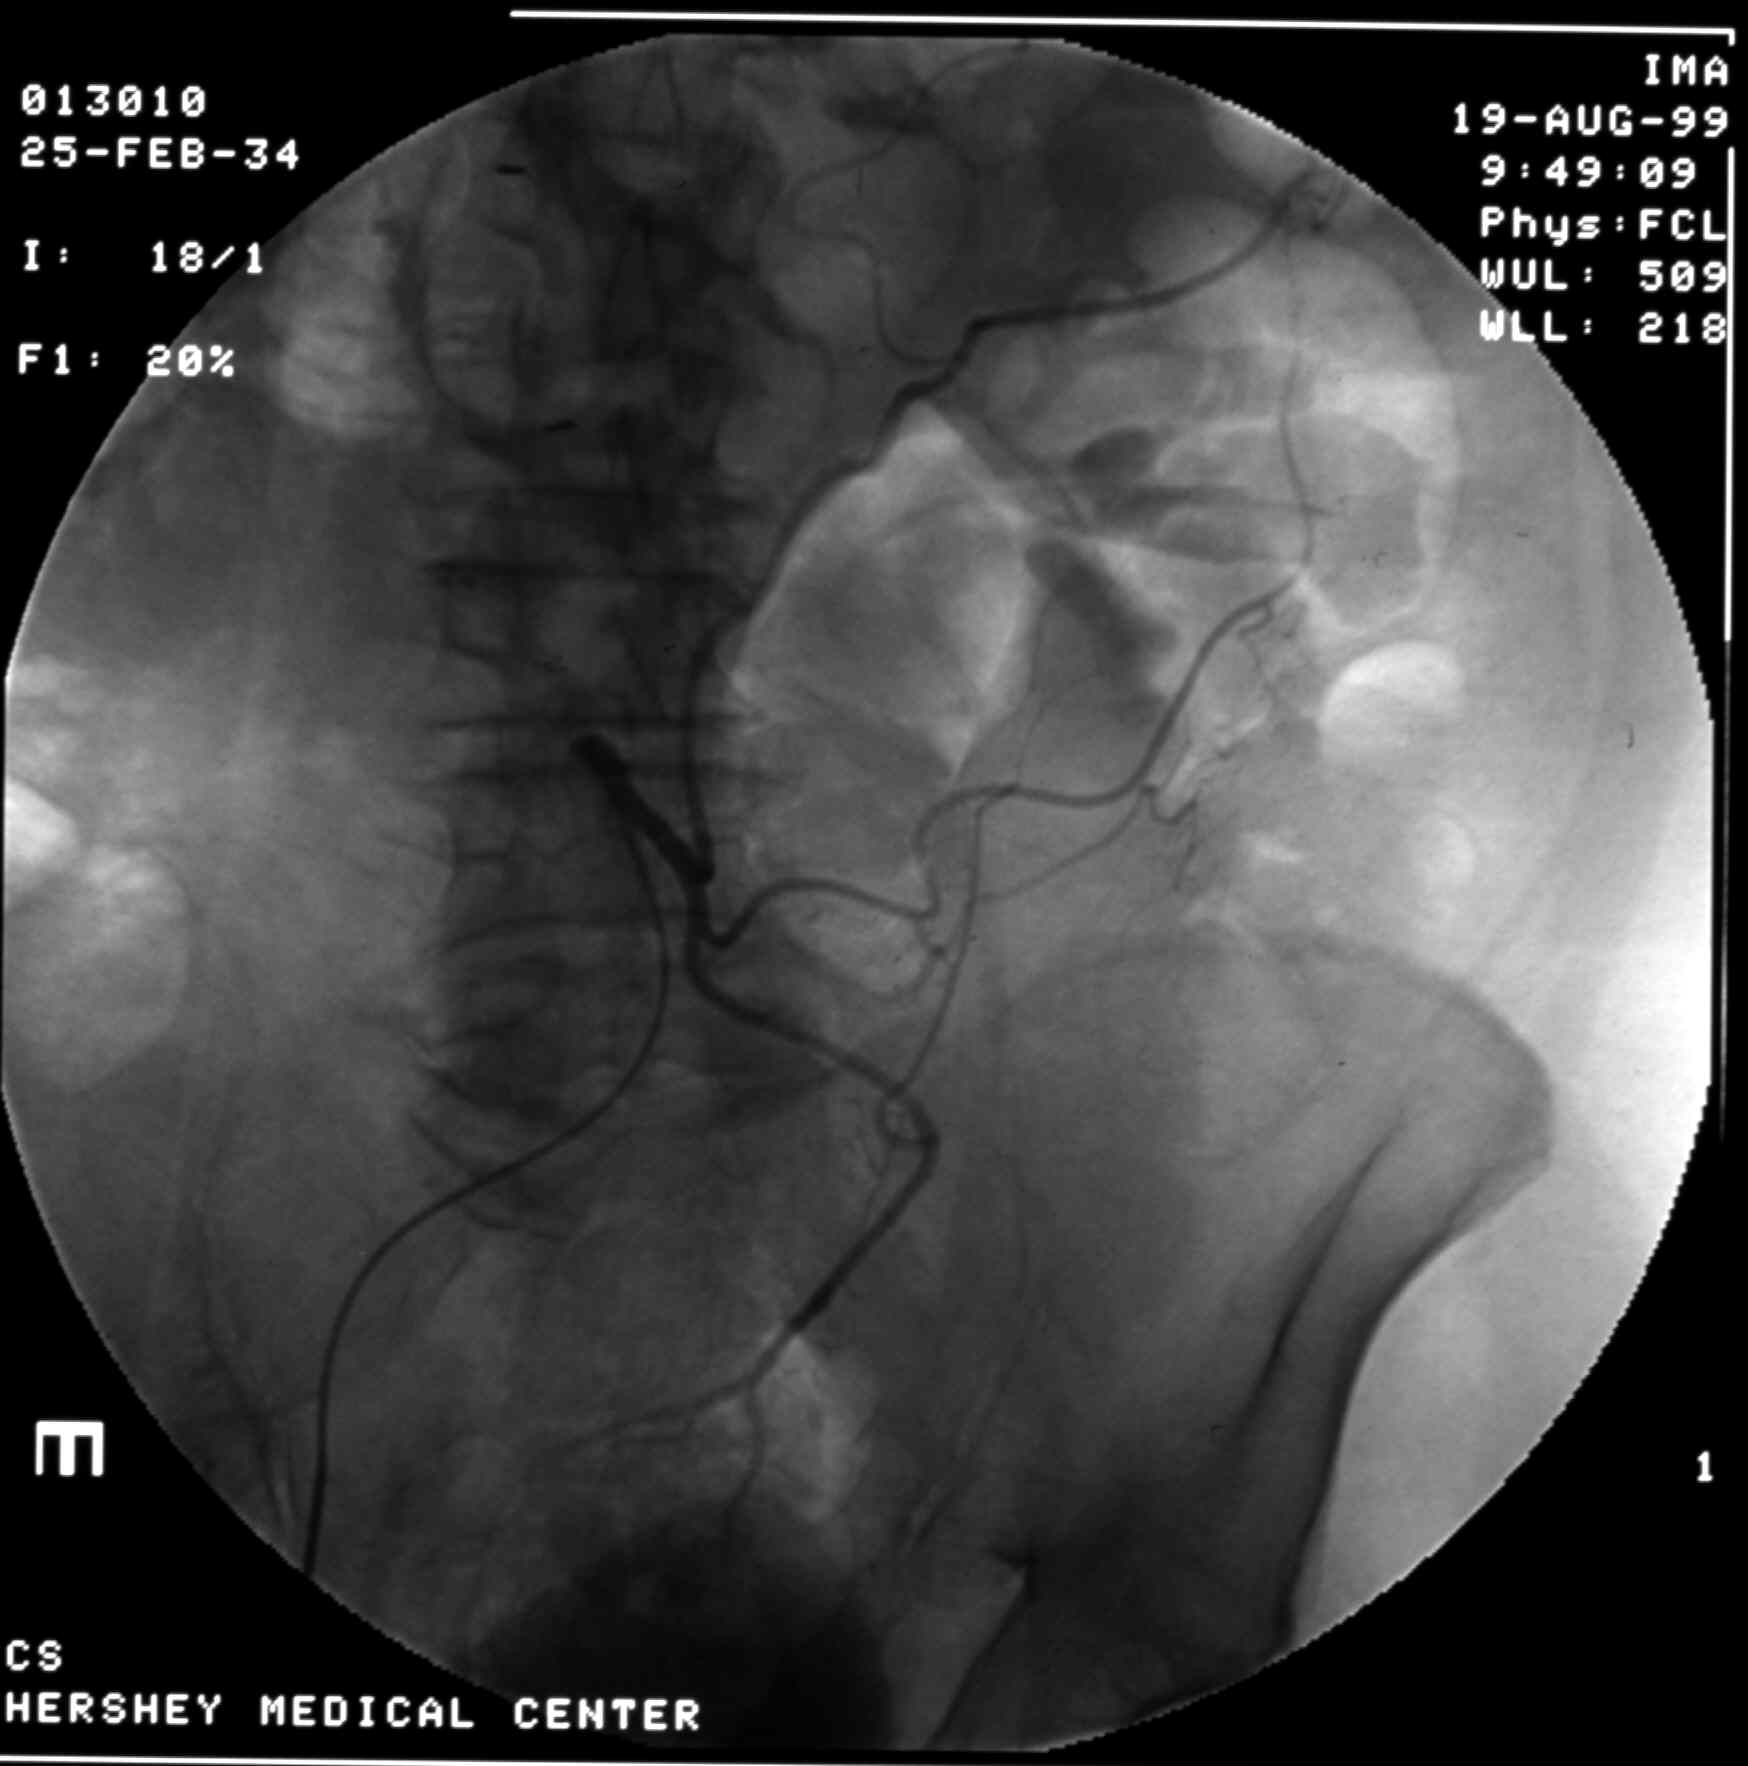

Inferior Mesenteric Arteriogram - Arterial Phase

Identify:  Inferior Mesenteric A., Left Colic A., Superior Rectal AA.